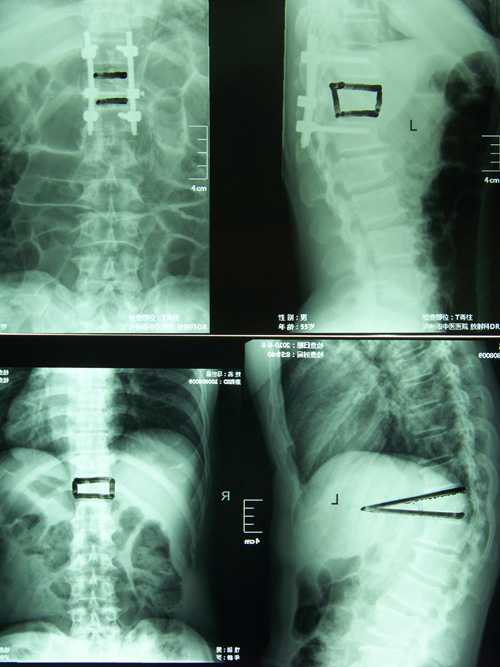

我科成功开展椎体形成术

骨伤一科成功开展经皮穿刺椎体成形术 骨伤一科 肖言洁 骨伤一科近日成功开展了高龄患者胸腰椎压缩性骨折经皮穿刺椎体成形术,该手术方式...